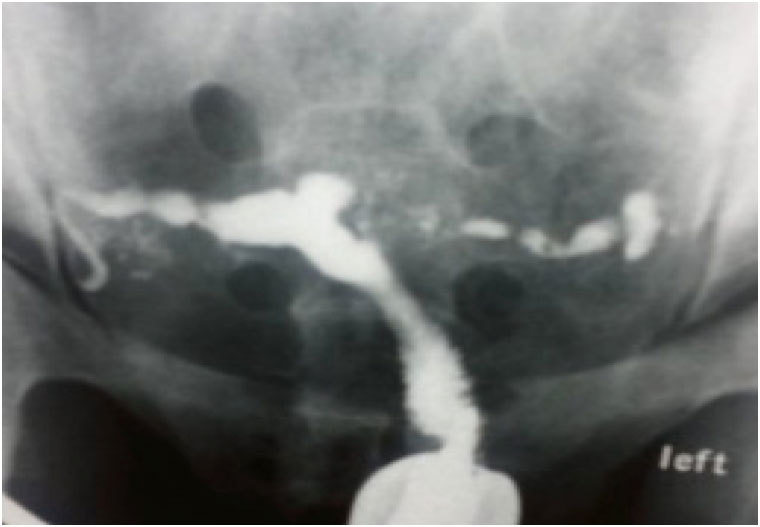

Хистеросалпингографията

- Класически рентгенов метод, който все по-рядко се използва.

- Контраиндикации – активна тазова инфекция, бременност, менструално кървене и алергия към контраста.

- 6-11 ден от менструалния цикъл при тънък ендометриум визуализира цервикалния канал, матката, тръбите, хидросалпингси, фимоза, перитонеално разливане на контраста.

- Болката при някои пациенти може да доведе до спирането на процедурата.

- Лъчево натоварване на малкия таз и яйчниците, вкл. гинеколога.

- Инфекция след HSG се среща до 3% от случаите, особено с патологични находки и серологично позитивни антитела /IgG/ за Chlamidia trachomatis.

- Doxicycline – профилактично намалява риска.

Проксималната тубарна оклузия – запушване на маточната тръба в началната стеснена част

- Среща се относително рядко

- Дължи се най-често на спазъм, запушване на маточната тръба от некротични материи, слузни запушалки или минимални адхезии.

- Селективната тубарна катетеризация се предлага в тези случаи.

- Рядко миомни възли в областта на маточния рог запушват проксимално фалопиевата тръба.

Дисталната тубарна оклузия – запушване в ампуларната част

- Специфична и честа находка при HSG.

- Висока корелация с лапароскопията.

- Различни степени на увреда – от фимоза до хидросалпингси

- Антитела за Хламидия са предпоставка за тубарна увреда и усложнения след процедурата.